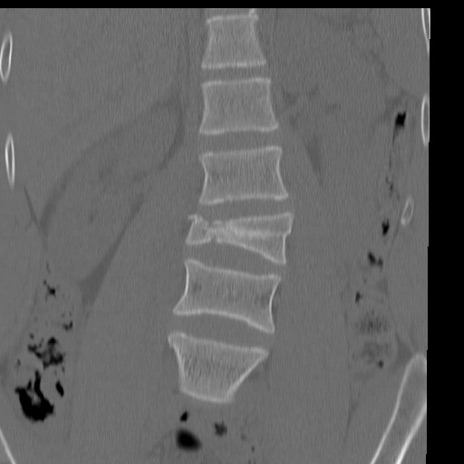

症例3 腰椎CT(冠状断像)

【症例】30歳代男性

【主訴】腰痛

【現病歴】本日旅行先で観光中に、友人と衝突し転倒し受傷。

【身体所見】麻痺なし、右下腿内側前面外側、左下腿内側に知覚鈍麻・しびれ

異常所見と診断は?

腰椎CT